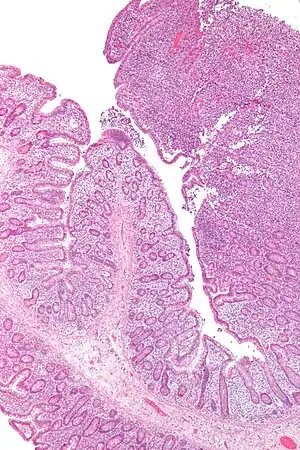

Micrograph of enteropathy-associated T cell lymphoma (upper right of image). H&E stain. | |